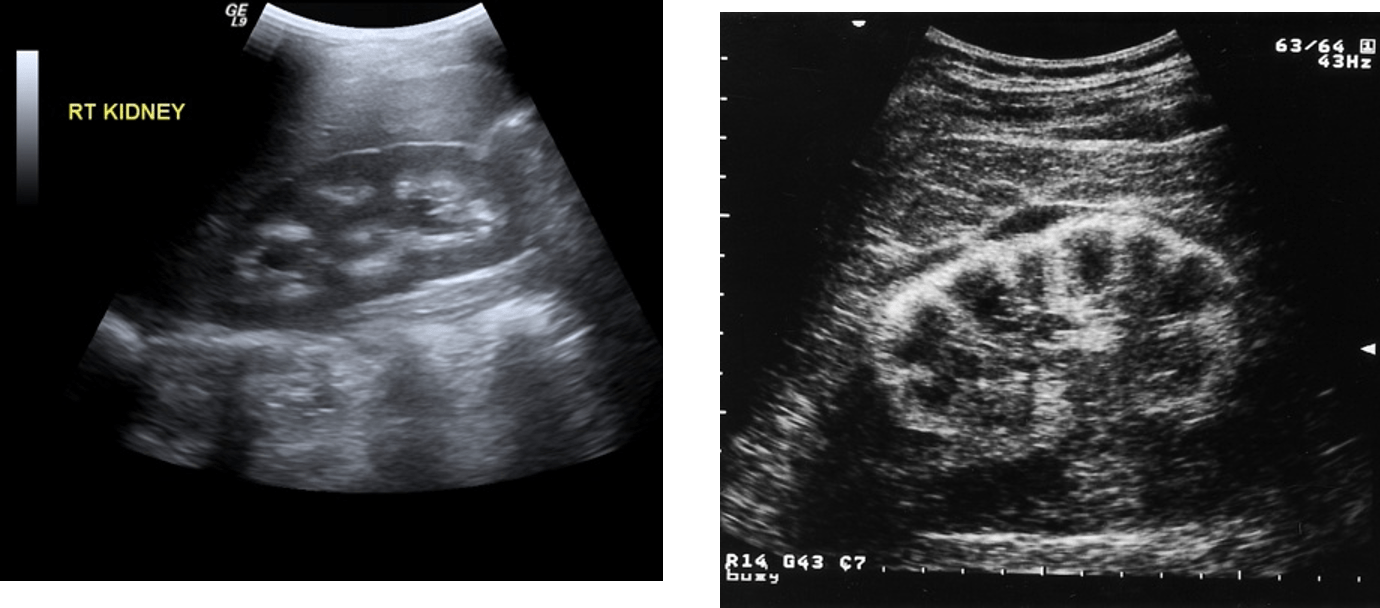

Determine the two different forms of nephrocalcinosis.

What is medullary nephrocalcinosis (left) and cortical nephrocalcinosis (right)?